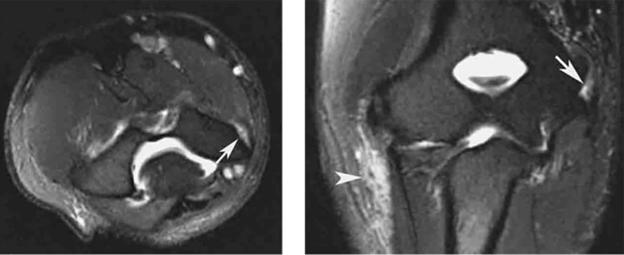

MRI Showing Elbow With Medial Epicondylitis

MRI images of medial epicondylitis showing inflammation of the tendons attached to the medial epicondyle (white arrow).

Reproduced from Amin NH, Kumar NS, Schickendantz MS. Medial Epicondylitis Evaluation and Management. J Am Acad Orthop Surg. 2015;23(6):348-355.